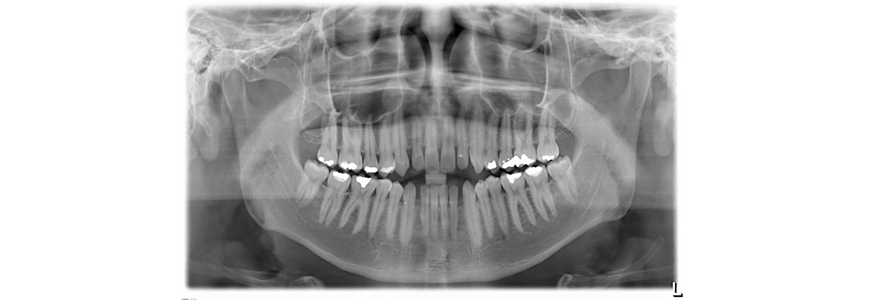

Es por ello que su análisis no solamente lo realiza viendo a su paciente sino que también requiere de ciertos estudios para confirmar el tipo de problema que tiene cada persona, profundizar sobre los tejidos, descartar presencia de quistes o tumores en los huesos, así como para establecer el plan de tratamiento que habrá de llevar a su paciente a una satisfacción de su tratamiento.

La importante necesidad de evaluar y revisar algunas radiografías de cara y cráneo, analizar una serie fotográfica clínica especial y analizar también unos moldes en yeso (replica de la boca del paciente en yeso), asegura un absoluto conocimiento del problema o de la serie de problemas que presente el paciente, tratando durante la terapia de corregir los problemas que más severidad se presenten en cada paciente.